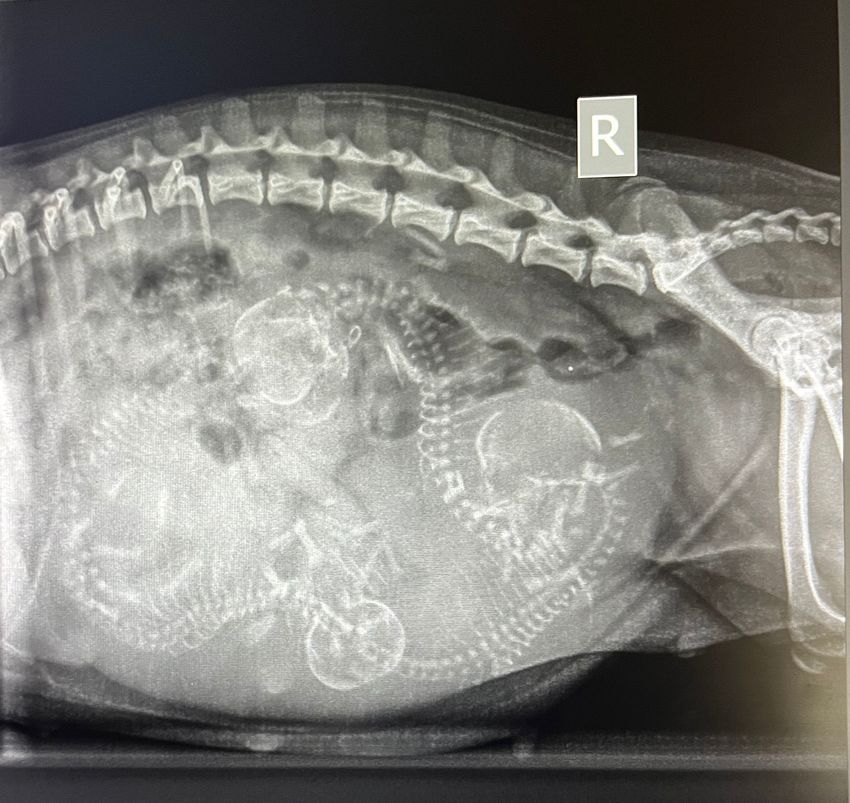

Als het gaat om dierenwelzijn, dan móét je je uitspreken - de hondjes kunnen het zelf niet - zodat mensen die dit topic lezen hopelijk beter nadenken en kiezen voor een gezonder hondenras. Door te stellen dat sommige mensen het beter weten, stel dat deze mensen mogelijk ongelijk hebben, maar er zijn zoveel rapporten inmiddels die aantonen dat de Chihuahua en vele andere rassen gewoon geen gezonde honden zijn. Tuurlijk zullen er Chihuahua's zijn, die gezond zijn en nergens last van hebben, maar kijk naar de foto en oordeel zelf.